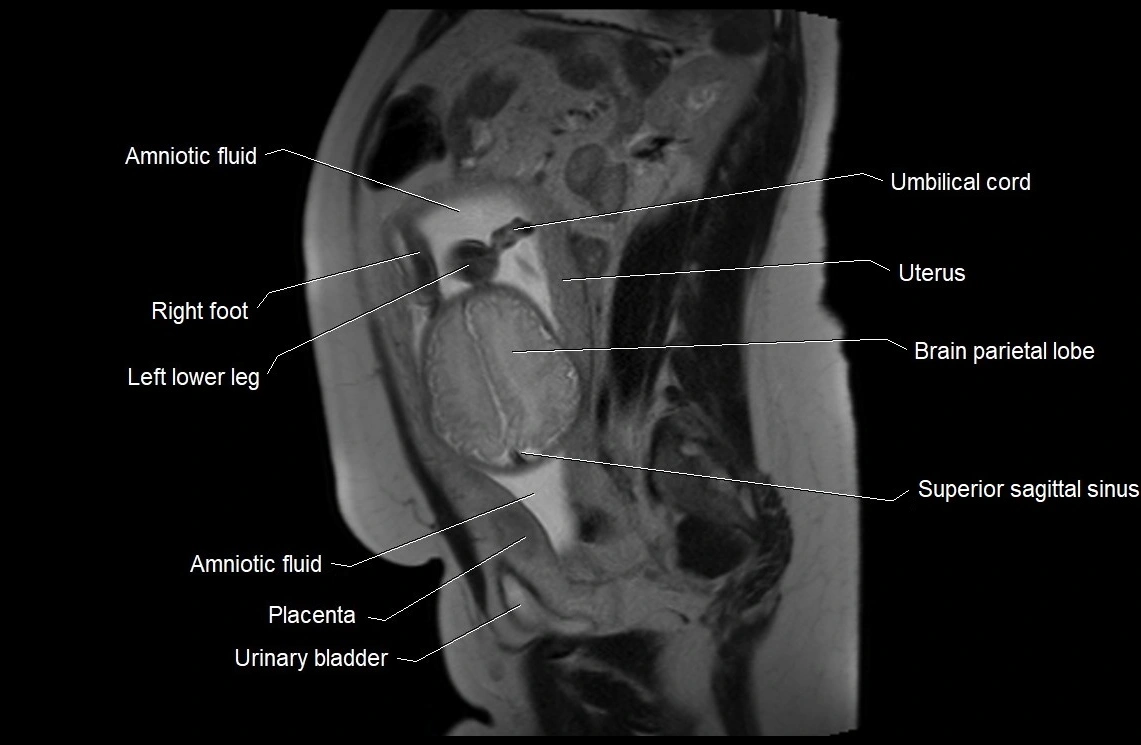

MRI Appearance

T2 HASTE (T2 GRE):

• Amniotic fluid shows very bright hyperintense signal

• Provides natural contrast against fetus and placenta

• Small particles (vernix) may appear as scattered hypointense foci within bright fluid

T1 GRE:

• Amniotic fluid shows low signal intensity (dark)

• Hemorrhage, infection, or proteinaceous content may cause focal or diffuse high signal intensity

MRI image

image